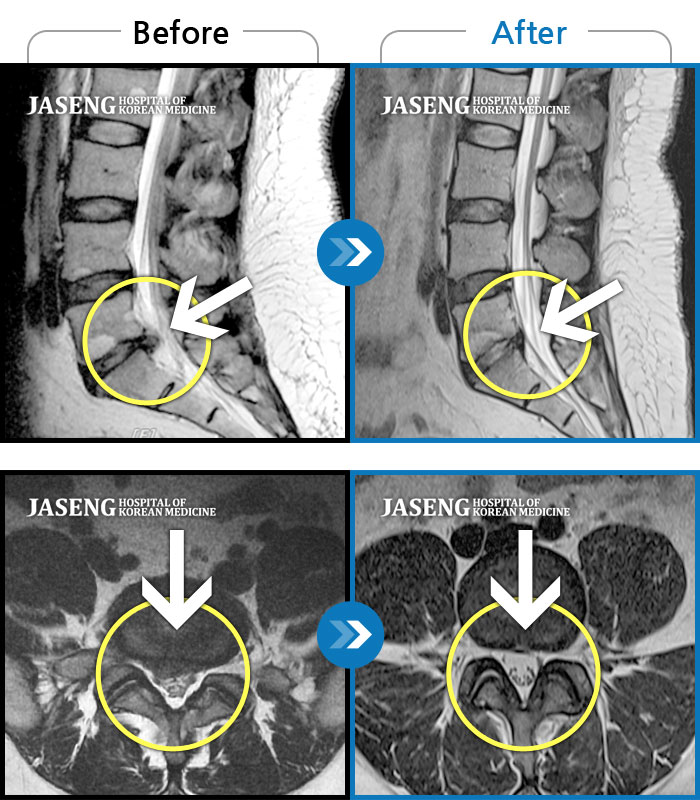

Before

After

환자에게 사전 동의를 받아 동일 조건에서 촬영되었습니다.

개인에 따라 치료 후 부작용이 발생할 수 있으니 의료진과 상담 후 치료를 진행하시기 바랍니다.

앉았다 일어날때 통증, 허리 당김

우측허리와 골반쪽의 통증으로 허리를 거의 90도 정도 구부려서 보행